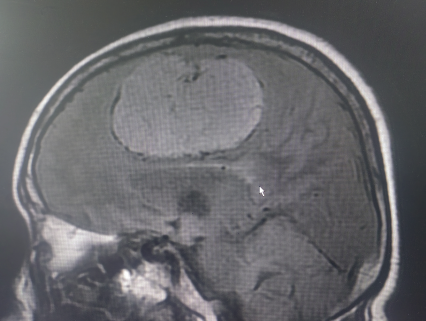

患者系中年女性,因出现偏侧肢体活动不灵和头痛症状,经检查发现颅内大脑镰旁长有一直径7cm的巨大肿瘤。肿瘤位于大脑的运动功能区,血供丰富,这一区域的手术风险极大。在决定手术治疗之前,神经外科医生与患者家属进行了充分的沟通,详细解释了手术的必要性、可能的风险和并发症,包括出血、感染、血管和神经损伤以及脑功能障碍等。家属在充分了解情况后,同意进行手术。面对这一复杂病例,我院迅速组织了由神经外科、麻醉科、心内科、输血科等多个科室的专家团队进行会诊,共同制定了先介入栓塞,再手术切除的治疗方案。

神经外科血管介入组曲友直副教授、崔刚副教授和高攀主治医师对肿瘤进行了瘤栓塞治疗,有效减少了肿瘤的血供,为后续的手术切除降低了风险。栓塞治疗后,神经外科王睿智副主任、高李贵副教授和董全主治医师在麻醉科、心内科、输血科等科室的全力配合下,凭借精湛的医术和丰富的临床经验,成功为患者切除了病变。手术过程中,麻醉科吕建瑞主任团队全程监控患者的生命体征,确保麻醉安全;心内科团队随时准备应对可能出现的心脏问题;输血科团队则确保充足的血液供应,以备不时之需。多学科的通力合作,为手术的成功提供了坚实的保障。